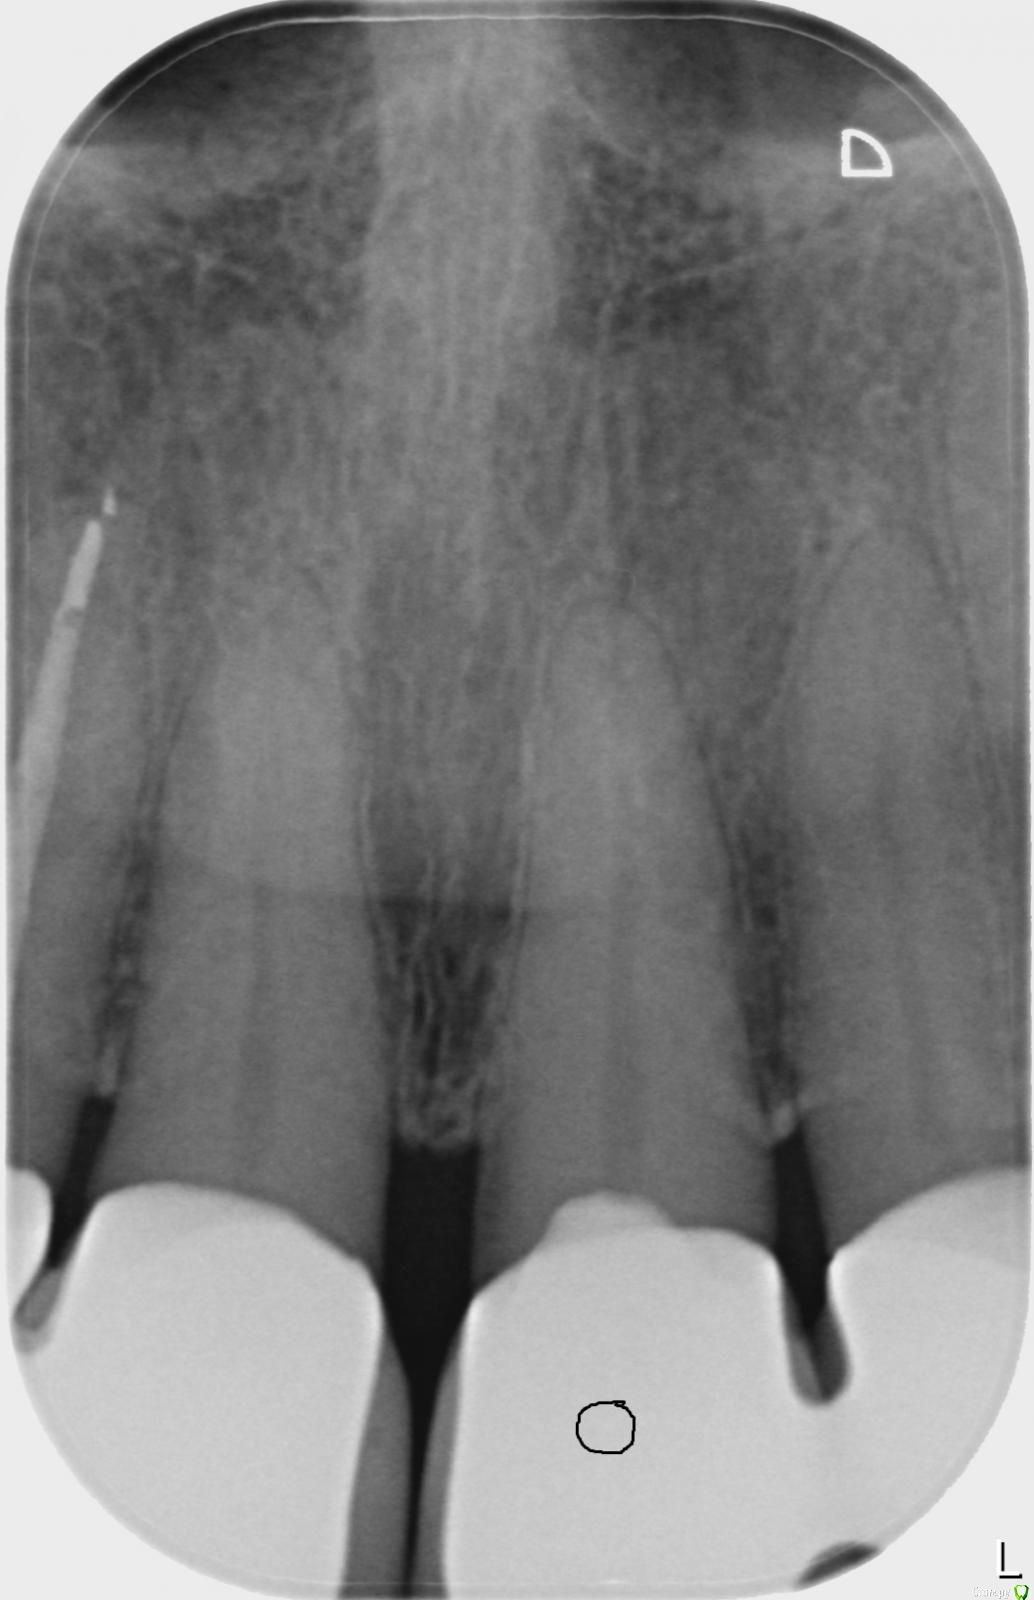

ellenchik Опубликовано 31 января, 2018 Автор Поделиться Опубликовано 31 января, 2018 Уважаемые доктора. Продолжу мою тему,к сожалению. В начале ноября зуб депульпировали-месяц ходила с лекарством. Боль так и не ушла. В декабре на приеме снова почистили, поставили лек-во еще на месяц. Боль периодически проходила ,потом возобновлялась снова. 8 января врач сказала, что с зубом все ОК,( хотя боль так и не прошла). Канал запломбировали, коронку закрыли пост. пломбой. Зуб болел как и прежде. Появилась небольшая боль при постукивании. На десятый день после пломбировки сделали снимок . По снимку она тоже проблемы не видит. С 18 янв . назначен Клиндазол 600 х 2 в день, 6 дней курс. После полного 6 дневного курса я жила 3 дня без боли. Сейчас уже снова все симптомы вернулись. Боль жгучая , ноющая, колющая, как будто заноза в челюсти над зубом ,или открытая рана, "растекается" иногда на два соседних зуба слева ( по рентгену они тоже вроде как ОК ), отдает в переносицу, усиливается ночью. Врач подозревает, что все же проблема в другом зубе. Но я почему-то четко чувствую этот зуб. Десна над зубом не отличается от других. Как же выяснить причину этой боли? Прицельные снимки, панорамный или комп. томография? Посмотрите,пожалуйста , снимок. Что-то можно по нему сказать? Огромное спасибо,что уделяете внимание и помогаете советами. Ссылка на комментарий

ellenchik Опубликовано 31 января, 2018 Автор Поделиться Опубликовано 31 января, 2018 Снимок от 17.01.2018. Ссылка на комментарий

red_butler Опубликовано 31 января, 2018 Поделиться Опубликовано 31 января, 2018 По снимку все хорошо, нужен очный осмотр Ссылка на комментарий

ellenchik Опубликовано 31 января, 2019 Автор Поделиться Опубликовано 31 января, 2019 Уважаемые доктора! Подниму свою старую тему, т.к. актуальна. Летом 2018 была у 2-х врачей на консультации. Ничего не нашли. Последние 3 недели снова обострились непонятные боли слева в районе 1-2-3 зубов. Но теперь больше над зубом № 3, именно НАД зубом - отдает вверх в переносицу . Такая разлитая ,жгучая,колющая боль. На холодное-горячее вроде как не реагирует. Болит спонтанно и ночью тоже. Врач смотрела - ничего не находит. Делала какую-то пробу над этим зубом чем-то типа бора - жужжащим приборчиком . Было прилично больно,как по нерву. Сказала,что это неплохо. По рентгену тоже говорит всё ОК. Свежий рентген прилагаю.Посмотрите пожалуйста. Есть еще КТ апреля 2018 в формате GALILEOS Viewer фирмы Sirona Dental SystemsВот ссылка https://dropmefiles.com/5XIaY (Эта проблема была уже тогда) Была бы очень признательна,если бы кто-нибудь глянул. С уважением Елена Ссылка на комментарий